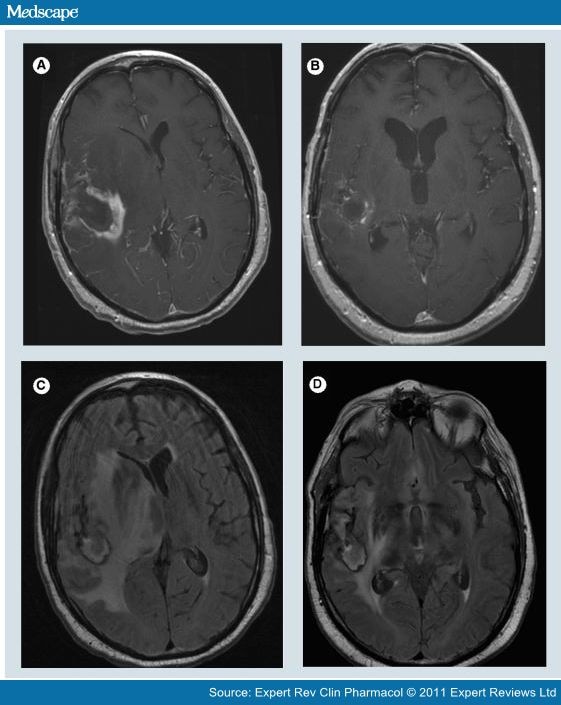

From www.medscape.com

Corticosteroids in Brain Cancer Patients Why Are Corticosteroids Given To Cancer Patients  There are a number of reasons you might have steroids as part of your cancer treatment. Corticosteroids have an established role in specific indications in cancer patients such as spinal cord compression,. Dexamethasone is a steroid medication. They are prescribed to reduce swelling and fatigue,. Why are steroids prescribed during cancer treatment? Corticosteroids are listed as emergent therapy for cord. Why Are Corticosteroids Given To Cancer Patients.

Corticosteroids in Brain Cancer Patients Page 3 Why Are Corticosteroids Given To Cancer Patients  They are prescribed to reduce swelling and fatigue,. Corticosteroids have an established role in specific indications in cancer patients such as spinal cord compression,. Glucocorticoids are commonly used in patients with cancer for symptom relief or as part of their anticancer treatment. Why are steroids prescribed during cancer treatment? Why are steroids used in cancer treatment? Steroids are used for. Why Are Corticosteroids Given To Cancer Patients.